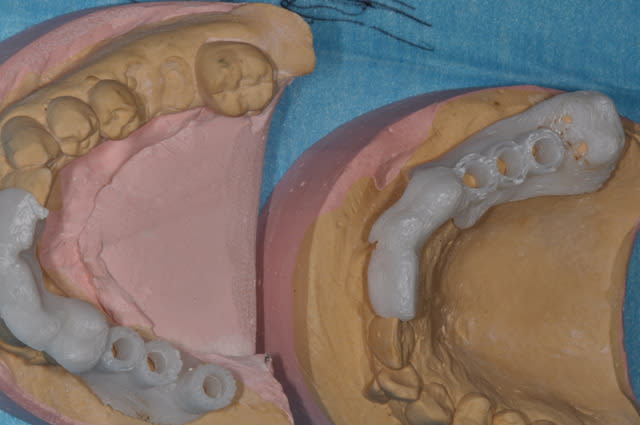

j'ai repris un ancien cas que j'avais posé avec un guide (blanc) et j'ai refait ce guide (splint)avec le nouvel add-on, la différence est vraiment importante et visible sur la photo3

La nouvelle technique simplifie aussi la planification.

Le nouvel add-on de Patrick est différent mais plus précis que l'ancien

il est possible de gérer:

l'épaisseur du guide.

le diamètre du cylindre et l'épaisseur de ce cylindre pour chaque implant

oui pour l'axe

oui tu connais la profondeur entre le bord du cylindre et l'apex de l'implant

Il serait simple d'incorporer des clefs mais je n'en comprends pas l'utilité pour des guides non métalliques

Le cout d'un guide étant dérisoire, en fonction des cas il m'arrive d'en faire plusieurs

Le matériau est de l'abs